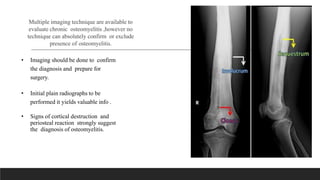

Multiple imaging technique are available to

evaluate chronic osteomyelitis ,however no

technique can absolutely confirm or exclude

presence of osteomyelitis.

• Imaging should be done to confirm

the diagnosis and prepare for

surgery.

• Initial plain radiographs to be

performed it yields valuable info .

• Signs of cortical destruction and

periosteal reaction strongly suggest

the diagnosis of osteomyelitis.